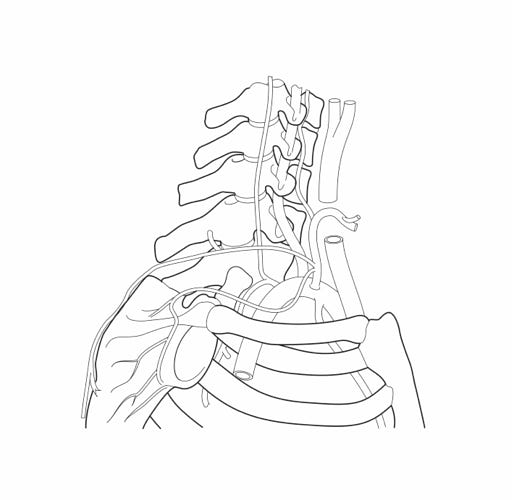

Über die Gefäße, Nerven und Faszien gelingt es, dem Menschen zu einer guten Regeneration zu verhelfen. Dies ist die Grundlage des Behandlungsprinzips Stärkung der Homöostase.